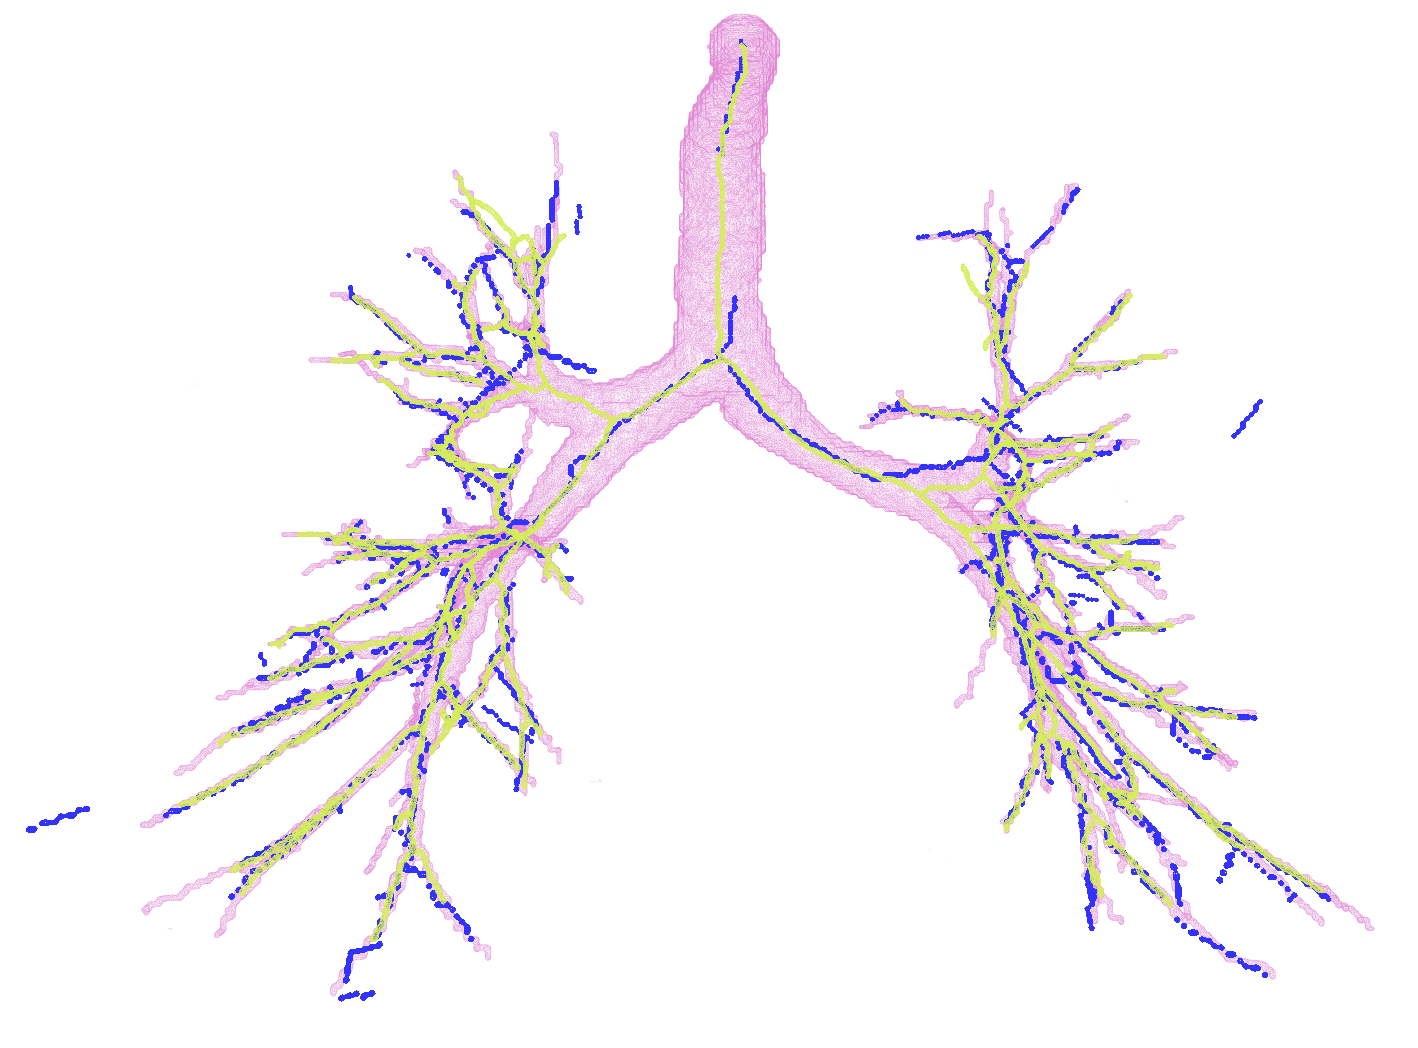

In Figure 2, first we present the predicted subgraph for one of the images. The gray dots are nodes of the over-complete graph with features, , extracted using Bayesian smoothing; the edges are colour-coded providing an insight into the performance of the method: yellow edges are true positives, red edges are false positives and blue edges are false negatives compared to the ground truth connectivity derived from the reference segmentations. Several of the false negatives are spaced closely, and in fact, do not contribute to the false negative error, , after generating the binary segmentations. The figure to the right in Figure 2 shows four predicted centerlines overlaid with the reference segmentation and centerlines from the voxel-classifier approach. Clearly, the MFN method is able to detect more branches as seen in most of the branch ends, which is also captured as the reduction in in Table 1. Some of the false positive predictions from MFN method appear to be a missing branch in the reference as seen in the first of the four scans. However, there are few other false positive predictions that could be due to the model using only pairwise potentials; this can be alleviated either by using higher order neighbourhood information or with basic post-processing. The centerlines extracted from MFN are slightly offset from the center of airways at larger scales; this could be due to the sparsity of the nodes at those scales and can be overcome by increasing resolution of the input graph.